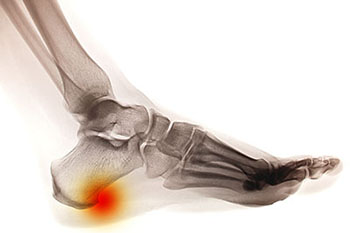

heel spur

Heel spurs are brought upon by a calcium deposit that causes a bony protrusion on the underside of the heel bone. It normally forms over time and can best be diagnosed through an x-ray examination. Heel spurs are commonly linked with plantar fasciitis, an inflammation that runs along the bottom of the foot. Common symptoms of heel spurs include pain towards the affected area, inflammation, and swelling at the front of the heel.